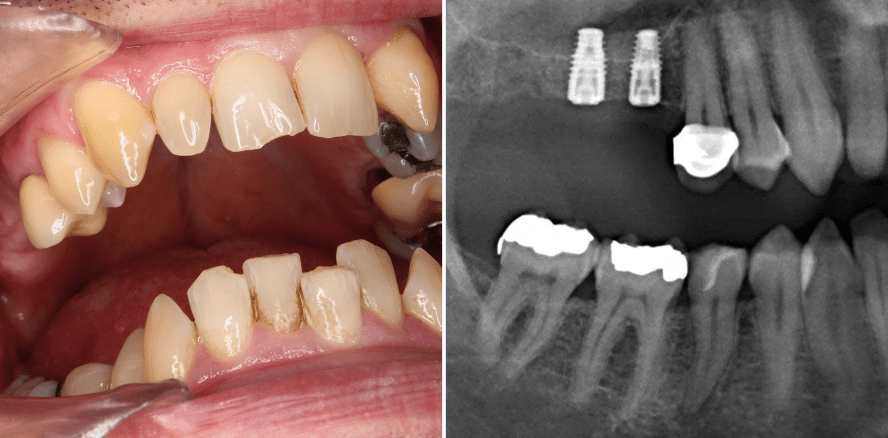

Am 26. Februar 2015 stellte sich der Patient für eine professionelle Zahnreinigung und Kontrolle vor. Der damals 50Jährige war anamnestisch als soweit unauffällig einzuordnen und nahm außer einem Blutdrucksenker (Zanipril) keine Medikamente regelmäßig ein. Aufgrund einer positiven Perkussion an Zahn 17 wurde ein Einzelzahnbild desselben angefertigt.

Nach vier Tagen kam der Patient dann zur Extraktion. Zunächst wurde die Brücke Regio 15/16 getrennt, dann wurde die Krone des Zahns 17 entfernt und eine tiefe kariöse Zerstörung bestätigt. Der Zahn wurde anschließend mittels Periotom sowie Bein’schem Hebel entfernt und die Wunde vernäht. Eine Eröffnung der Kieferhöhle konnte ausgeschlossen werden. Circa acht Monate später entschied sich der Patient auf Empfehlung des behandelnden Zahnarztes, den Zahn 18 extrahieren zu lassen. Dieser wies distal eine kariöse Zerstörung auf, war bereits im Sinne einer großen Amalgamfüllung okklusal therapiert worden und hatte keinerlei Bedeutung für das geplante prothetische Konzept, das sich auf zwei Einzelzahnimplantate Regio 16 und 17 konzentrierte. Demnach wurde der Zahn 18 komplikationslos entfernt. Ende Februar 2017 wurden dann zwei Implantate Regio 16 und 17 (SIC) gesetzt sowie ein Intralift bzw. Physiolift mittels Piezoelektrischer Chirurgie durchgeführt. Mithilfe eines Safescrapers und apikaler Knochenreduktion mit Piezo wurde Eigenknochen gewonnen und dieser für eine laterale Augmentation verwendet. Beide Implantate waren primärstabil.